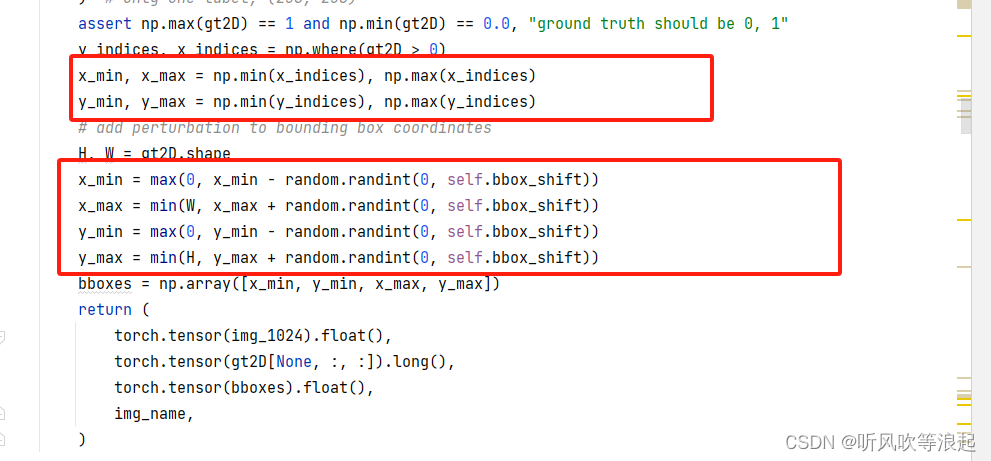

对于bbox提示边界框,也很简单,对前景取值即可,取x,y最小、最大,加个修正偏移即可

bbox在数据上的表现就类似于画框,将图像指定区域框出来,所以输入的维度就多加了1